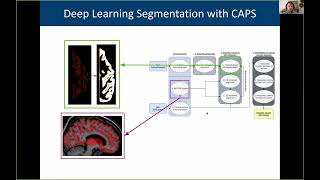

3D reconstruction and visualization techniques for primate brains

3D reconstruction and visualization techniques for primate brains 3D reconstruction and analysis of the macaque brain from histological slices

3D reconstruction and analysis of the macaque brain from histological slices Thomas Funck: 3D reconstruction